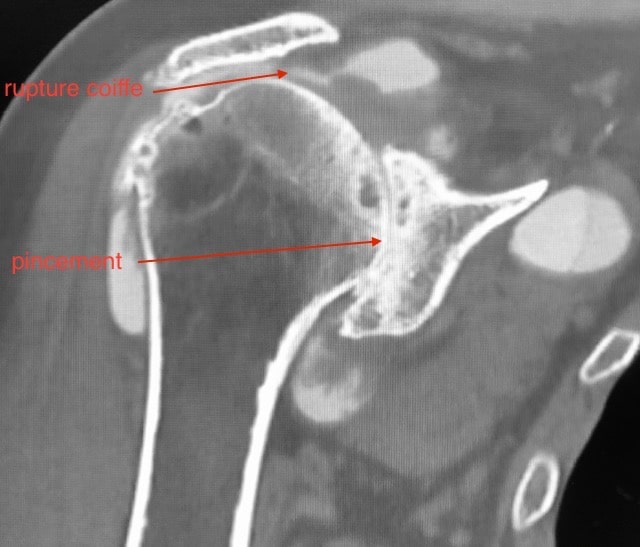

Usure de la coiffe des rotateurs

Rupture de la coiffe des rotateurs

La coiffe des rotateurs est le nom d’un ensemble de tendons (sous scapulaire, sus-épineux, sous-épineux et petit-rond) situés sur la tête de l’humérus et dont la fonction est essentielle dans la mécanique de l’épaule. La coiffe peut être le siège d’une lésion, d’une déchirure, soit progressive, appelée rupture dégénérative (usure), soit plus rarement liée à un traumatisme (rupture traumatique). Elle concerne soit un seul tendon, fréquemment le sus-épineux, soit deux ou trois tendons.

Cette rupture est dite rupture partielle lorsqu’elle ne touche que partiellement le tendon, ou rupture complète (transfixiante), quand elle le traverse de part en part.

Une radiographie permet de poser le diagnostic, lorsqu’est mis en évidence un pincement et l’apparition de becs osseux (ostéophytes). Ces derniers peuvent avoir pour conséquence une irritation et une usure du tendon de la coiffe des rotateurs. Un kyste synovial peut également apparaître. L’IRM permet de préciser le diagnostic et explore arthrose, bec osseux, kyste et état de la coiffe.